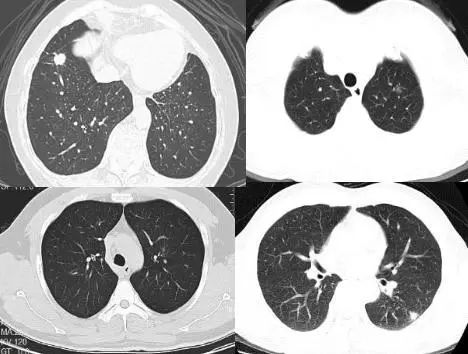

影像学示直径≤3 cm的局灶性、类圆形、密度增高的实性或亚实性肺部阴影。可为孤立或多发,不伴肺不张、肺门淋巴结肿大和胸腔积液。局部病灶直径>3 cm者则称为肺肿块。

单个病灶定为孤立性,孤立性肺结节为边界清楚、密度增高、直径≤3 cm且周围被含气肺组织包绕的软组织影;2个以及以上的病灶定义为多发性,需要与转移性肺肿瘤鉴别诊断。

实性肺结节(solid nodule),间质血管都看不见(左上图),亚实性肺结节(subsolid nodule)包括纯磨玻璃结节(pure ground-class nodule,pGGN)(左下图),还有混杂性结节(mixed ground-glass nodule,mGGN),也称部分实性结节(part solid nodule),表现为间质样改变,中间实性,周围是磨玻璃样。